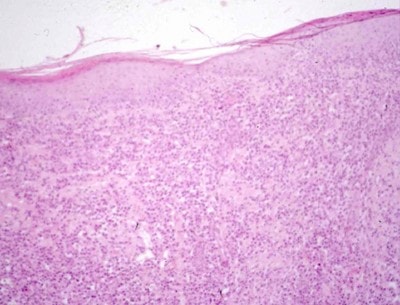

Examen histopathologique de biopsies cutanées (Photos 3 et 4)

L’analyse histopathologique révèle un pattern de dermatite nodulaire avec un infiltrat composé quasi-entièrement de plasmocytes, certains d’entre eux contenant des inclusions éosinophiles correspondant à des immunoglobulines (corps de Russel). Dans ce contexte clinique, ce tableau histopathologique est fortement évocateur de pododermatite plasmocytaire.

Photo 3

Photo 4